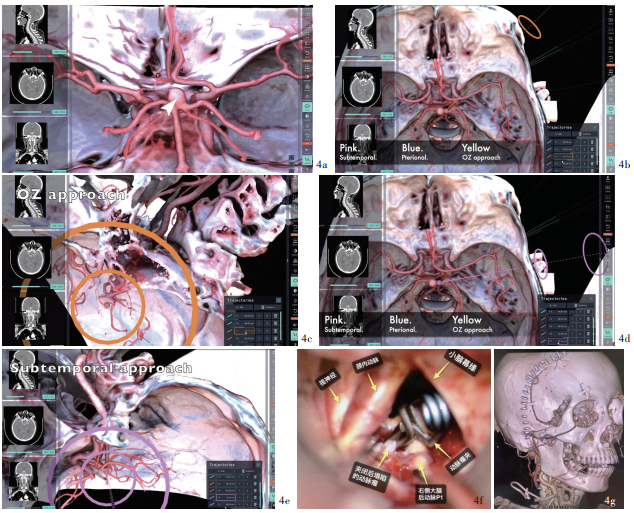

Background: Neurosurgery developed rapidly with technology advancing. Concept of digit-intelligent neurosurgery becomes mature and augmented reality (AR) technology shows great potential in future neurosurgical operations. The feasibility and applicability of AR assisted technology is currently the most important topic in clinical research. Methods: Four cases engaged from January to December 2024 in Department of Neurosurgery of Beijing Tsinghua Changgung Hospital with vestibular schwannoma (one case), intracranial aneurysm (2 cases) and subclavian artery (SA) occlusion caused vertebral artery steal syndrome (one case) have been conducted tumor resection, internal carotid artery (ICA)-posterior communicating artery (PCoA) aneurysm clipping and common carotid artery (CCA)-SA bypass, respectively. Using presurgical imaging data-based Surgical AR reconstruction on the HoloLens 2 platform, preoperative planning, surgical simulation, and intraoperative display were conducted. These were then compared with surgical practices and postoperative imaging data to qualitatively evaluate their effectiveness in assisting neurosurgery. Results: 1) Vestibular schwannoma resection: compared to the preoperative AR assisted simulation, we fully replicated the procedures of retrosigmoid approach craniotomy, removal of the posterior wall of internal auditory canal, and the exposure and removal of the internal auditory canal tumor during surgical practice. Facial nerve function was preserved intact during the surgery and reached House-Brackmann grade Ⅰ, but effective hearing was not preserved. Postoperative imaging data showed non-significant difference compared to preoperative simulation and surgical practice. The modified Rankin Scale (mRS) assessed postoperatively was 2. 2) ICA-PCoA aneurysm clipping: compared to the presurgical AR assistance, we fully replicate the procedures of lateral supraorbital craniotomy, removal of anterior clinoid process and the exposure and clipping of the neck of aneurysm. Postoperative imaging data showed non-significant difference compared to preoperative simulation. Postoperatively symptoms such as eye pain, ptosis, and double visian were completely relieved and the mRS was 0 after 6 months. 3) Basilar artery apex aneurysm clipping: based on preoperative simulation, we opted for the orbito-zygomatic approach during surgery to provide full exposure of the aneurysm neck and direct visualization of the bilateral P1 segment of posterior cerebral artery (PCA), offering better safety compared to the subtemporal approach. In surgical practice, lateral sulcus was separated, basilar artery and aneurysm was exposed and clipped via carotid spaces. Postoperatively occlomoter nerve was well recovered mRS was 0 after 6 months. 4) CCA- SA bypass: critical muscles and vessels on the neck were located intraoperatively on the body surface with AR assistance. CCA and SA were fully exposed and artificial vessel was anastomosed. Postoperative CTA 3D reconstruction suggested the blood flow was patent. The dizziness did not recur, and the blood pressure in the upper limb on the affected side returned to normal. Postoperative mRS was 0 after 6 months. Conclusions: The application of AR technology in neurosurgical procedures allows for preoperative planning, surgical simulation, and intraoperative display. It aids young surgeons in quickly understanding complex anatomical structures and shortens the learning curve, holding significant clinical value and promising application prospects.

研究背景: 计算机技术和人工智能技术的发展使数智神经外科学日趋成熟, 增强现实技术作为新兴技术已在神经外科手术中展现出巨大潜力, 探讨该项技术辅助神经外科手术的可行性和实用性将是现阶段临床研究的重要议题。方法: 纳入4例2024年1-12月在清华大学附属北京清华长庚医院行神经外科手术的前庭神经鞘瘤(1例)、颅内动脉瘤(2例)和锁骨下动脉闭塞致椎动脉盗血综合征(1例)患者, 分别接受前庭神经鞘瘤切除术、颈内动脉-后交通动脉动脉瘤夹闭术和颈总动脉(CCA)-锁骨下动脉(SA)搭桥术; 将术前常规影像学数据导入Surgical AR软件, 基于HoloLens 2平台进行术前规划、模拟手术和术中实时显示, 并与实际手术操作和术后影像学数据对比, 定性分析增强现实技术辅助神经外科手术的疗效。结果: (1)前庭神经鞘瘤切除术: 与术前增强现实技术模拟手术(模拟手术)对比, 实际手术完全复现经枕下乙状窦后入路开颅、内耳道后壁磨除、内耳道内肿瘤显露和切除的操作过程, 术中面神经保护完好, 术后面神经功能达House-Brackmann分级Ⅰ级, 但未保留有效听力; 术后1周三维重建CT与术前模拟和术中实际所见无明显差异; 术后6个月改良Rankin量表(mRS)评分为2分。(2)颈内动脉-后交通动脉动脉瘤夹闭术: 与术前模拟手术对比, 实际手术完全复现经眶上外侧入路开颅、磨除前床突、显露动脉瘤颈并夹闭的手术过程; 术后三维重建CTA与术前模拟无明显差异; 术后6个月, 眼部胀痛、上睑下垂、复视等症状完全缓解, mRS评分为零。(3)基底动脉尖动脉瘤夹闭术: 根据术前模拟结果, 经眶颧入路对动脉瘤颈的显露更充分且术者可于直视下完全夹闭动脉瘤并保护双侧大脑后动脉P1段, 操作安全性明显优于经颞下入路; 实际手术中选择经眶颧入路, 分离外侧裂经颈内动脉-动眼神经间隙显露基底动脉和动脉瘤、夹闭动脉瘤; 术后6个月mRS评分为零, 动眼神经功能恢复良好。(4)CCA-SA搭桥术: 术中通过增强现实技术辅助颈部重要肌肉、血管体表定位, 充分显露颈总动脉和锁骨下动脉, 人工血管吻合; 术后三维重建CTA显示桥血管通畅; 患者头晕症状未再发作, 患侧上肢血压恢复正常; 术后6个月mRS评分为零。结论: 增强现实技术用于神经外科手术可术前手术规划、手术模拟和术中引导, 有助于青年医师快速理解复杂的解剖结构、缩短学习曲线, 具有重要的临床价值和广阔的应用前景。